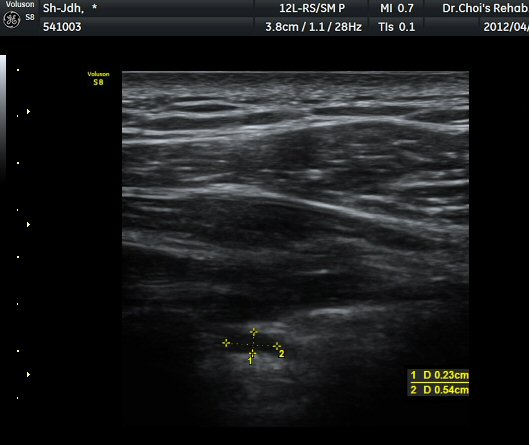

ÃÊÀ½ÆÄ °Ë»ç ; ³¶Á¾ÀÇ Å©±â°¡ Å©°Ô(1/5) ÁÙ¾îµë

ÈíÀÎ Àü ³¶Á¾ÀÇ Å©±â

ÈíÀÎ 5ÀÏ ÈÄ ³¶Á¾ÀÇ Å©±â